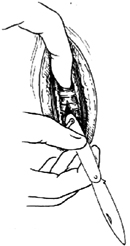

| 2-4 自下向上挑开气管第3~4软骨环 |

| 图2 气管切开术 |

5.切开气管环 用尖刀在气管前正中线切开气管的第3~4(或4~5)软骨环,切开时刀刃应朝上,自下向上挑开[图2-4],刀尖不可刺入太深,以2~3mm为宜。当咳嗽时,食管前壁连同气管后壁可挤向气管腔内[图2-5],因此,应趁咳嗽声刚停止的吸气过程中迅速切开。